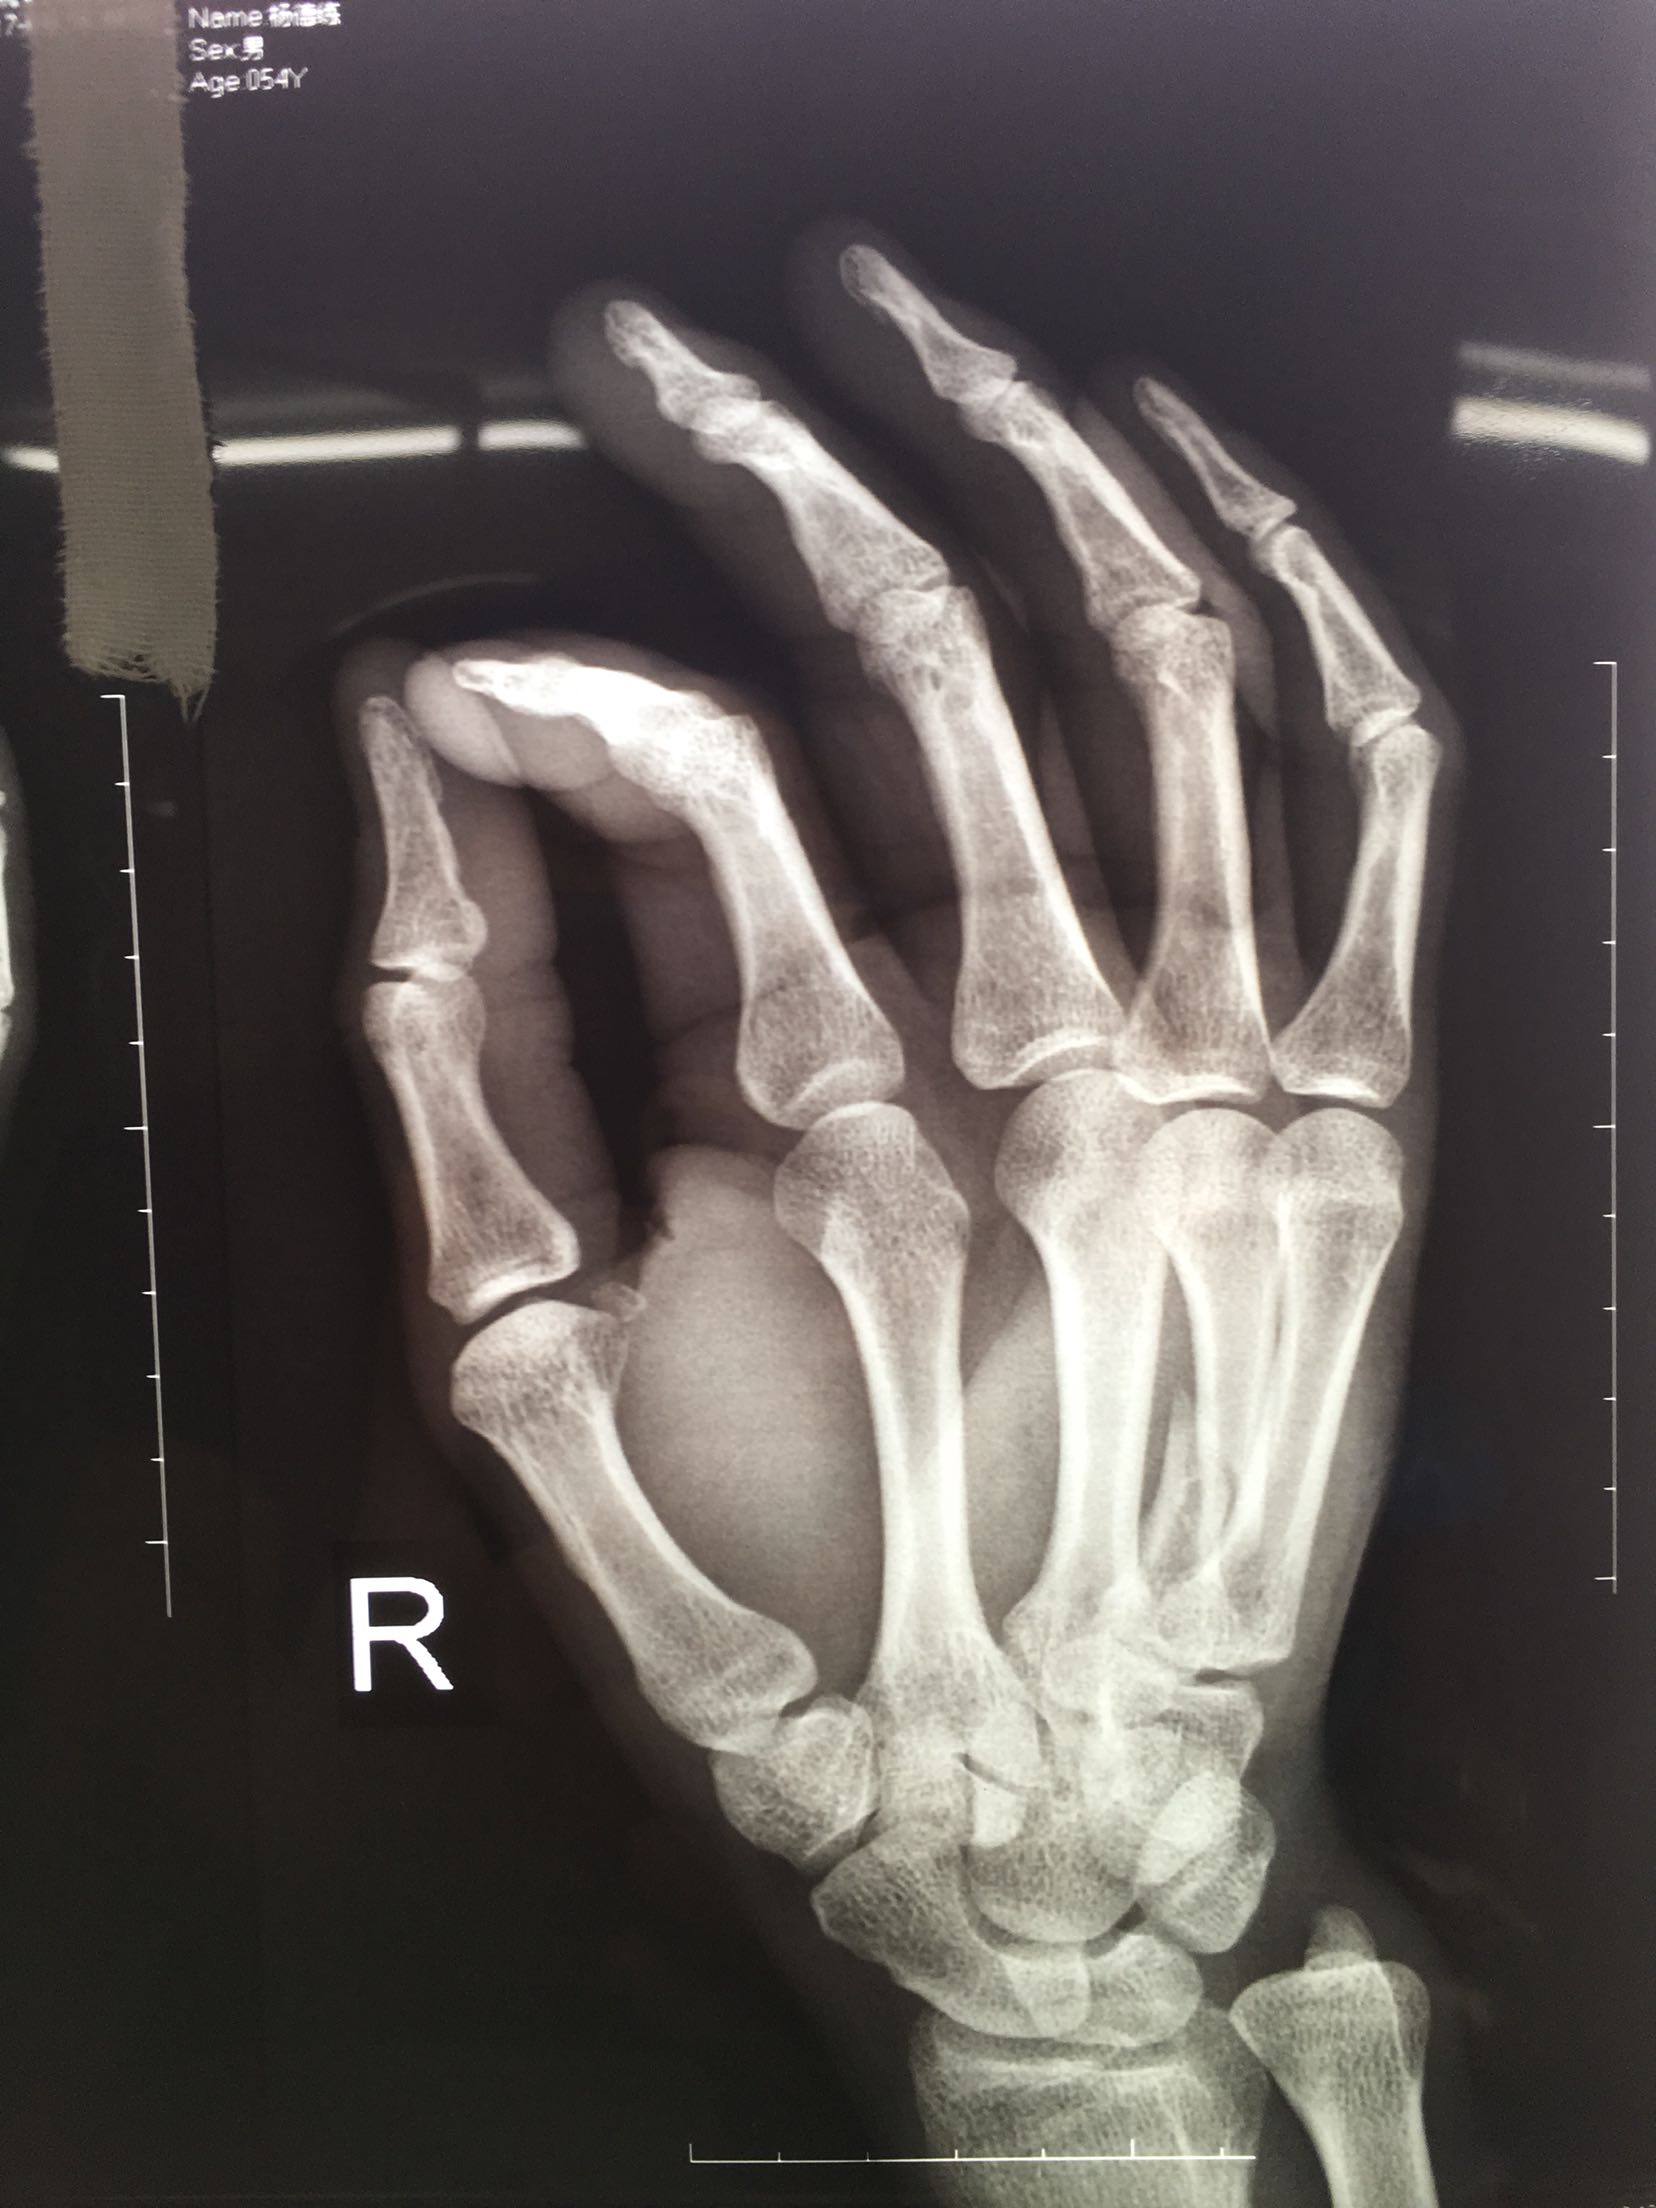

患者,男,52岁,摔伤后右手肿痛,活动受限4小时入院。

右手掌肿胀明显,皮色皮温正常,局部压痛,纵叩痛阳性,可及骨擦感,第四掌指关节活动受限,末梢血运感觉正常。

完善检查,在臂丛麻醉下行切复内固定术,术后抗炎,消肿止痛处理。